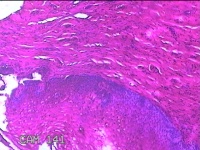

宫颈12点组织

性别

女

年龄

46岁

临床诊断

人乳头瘤病毒感染

一般病史

人乳头瘤病毒其他12高危型阳性

标本名称

大体所见

灰白暗红色组织0.8x0.5x0.2cm一块。